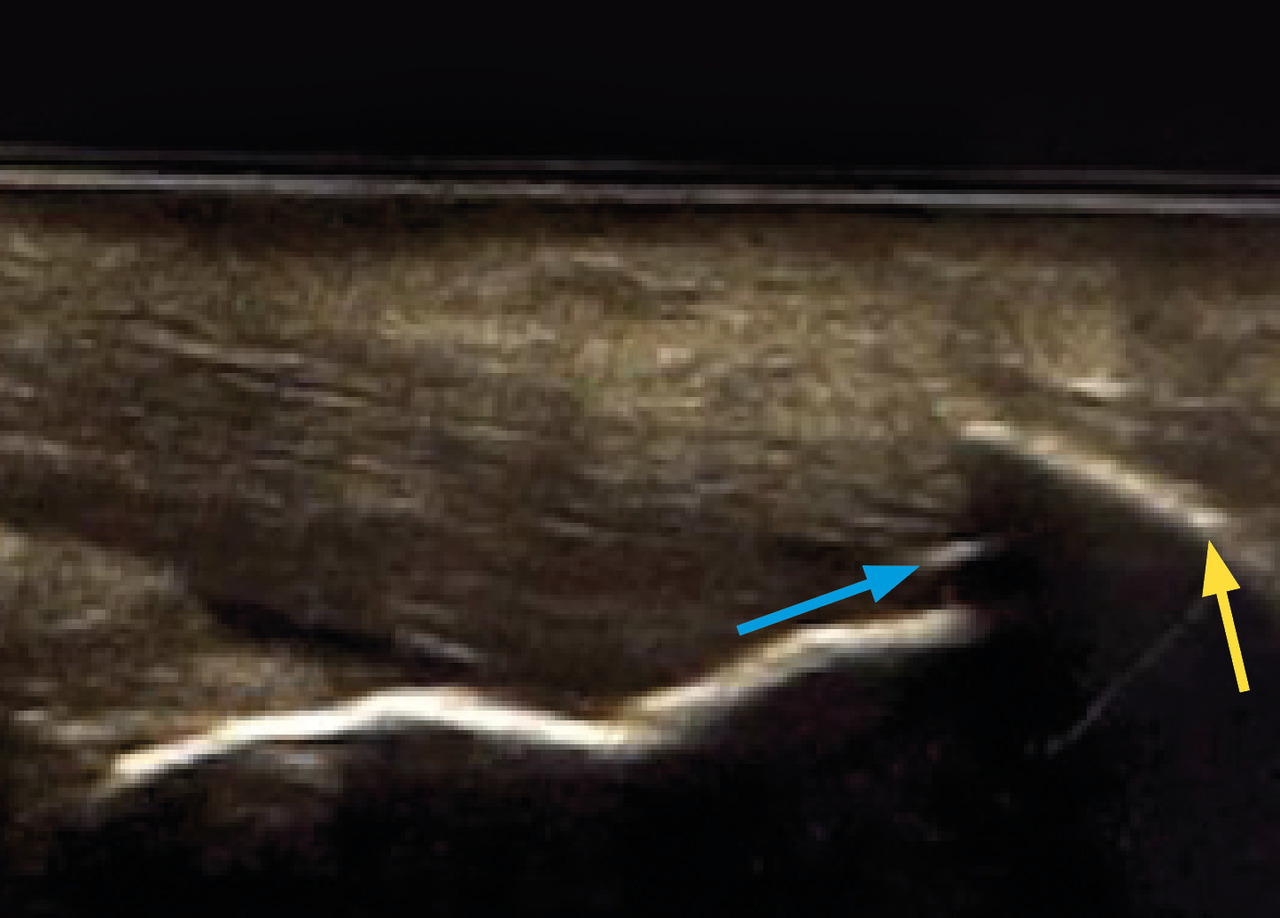

Aspect échographique normal

En utilisant le mode « brillance » (ou mode B) de l’échographe, le tendon calcanéen d’aspect normal a une structure fibrillaire, il est non épaissi, bien délimité et légèrement plus échogène que le tissu adipeux (fig. 1). Le mode « Doppler » ne met en évidence aucune anomalie.

En cas de tendinopathie calcanéenne, le tendon calcanéen perd son aspect fibrillaire. Il est épaissi de manière localisée ou diffuse. Il peut être mal délimité et prend un aspect hypoéchogène (fig. 2).

L’échographie peut révéler des signes associés tels qu’un enthésophyte (néoformation osseuse qui prend son origine sur la moitié distale de la corticale osseuse et se traduit par une image linéaire hyperéchogène), une calcification intratendineuse (image hyperéchogène avec un cône d’ombre postérieur) [fig. 2], une érosion (interruption focalisée de la corticale osseuse, visible sur deux plans de coupe perpendiculaires) ou une bursopathie pré- ou rétroachilléenne (plage prétendineuse dont l’échogénicité est variable en fonction de la quantité de liquide présente dans la bourse et de l’épaisseur de sa paroi).23,24